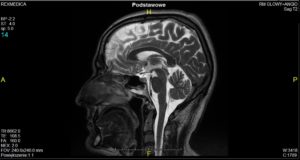

Ból głowy, a rezonans magnetyczny

Aby dokładnie zdiagnozować, co jest przyczyną częstych i uporczywych bólów głowy należy wykonać badanie za pomocą rezonansu magnetycznego. Jednym z takich miejsc, gdzie można to zrobić, jest warszawskie Centrum Rezonansu Magnetycznego Rex Medica. Wynik tego badania będzie pomocny dla lekarza specjalisty, np. neurologa, w przeprowadzeniu terapii.

Badanie głowy.

Dzięki badaniu głowy rezonansem magnetycznym można najbardziej dokładnie ocenić tkankę mózgową (uwidacznia istotę białą i szarą korową), struktury mózgowia (w szczególności tylnej jamy czaszki), układ komorowy, zbiorniki płynowe, struktury głębokie mózgu, a także wewnątrzczaszkowe odcinki nerwów czaszkowych.